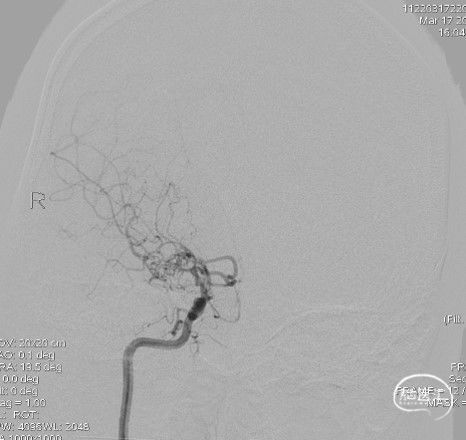

右侧颈内动脉正位:

造影:右侧颈内动脉末端变细,大脑前及大脑中自起始部闭塞,脑底少量烟雾血管形成,汇聚使R-MCA少量分支显影。